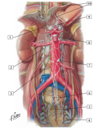

5

5 - internal thoracic vein

6

6 - inferior epigastric veins

7

7 - superficial epigastric vein

8

8 - superficial epigastric vein

9

9 - thoraco-epigastric vein

10

10 - lateral thoracic vein

11

11 - jugular veins (external, internal, anterior)